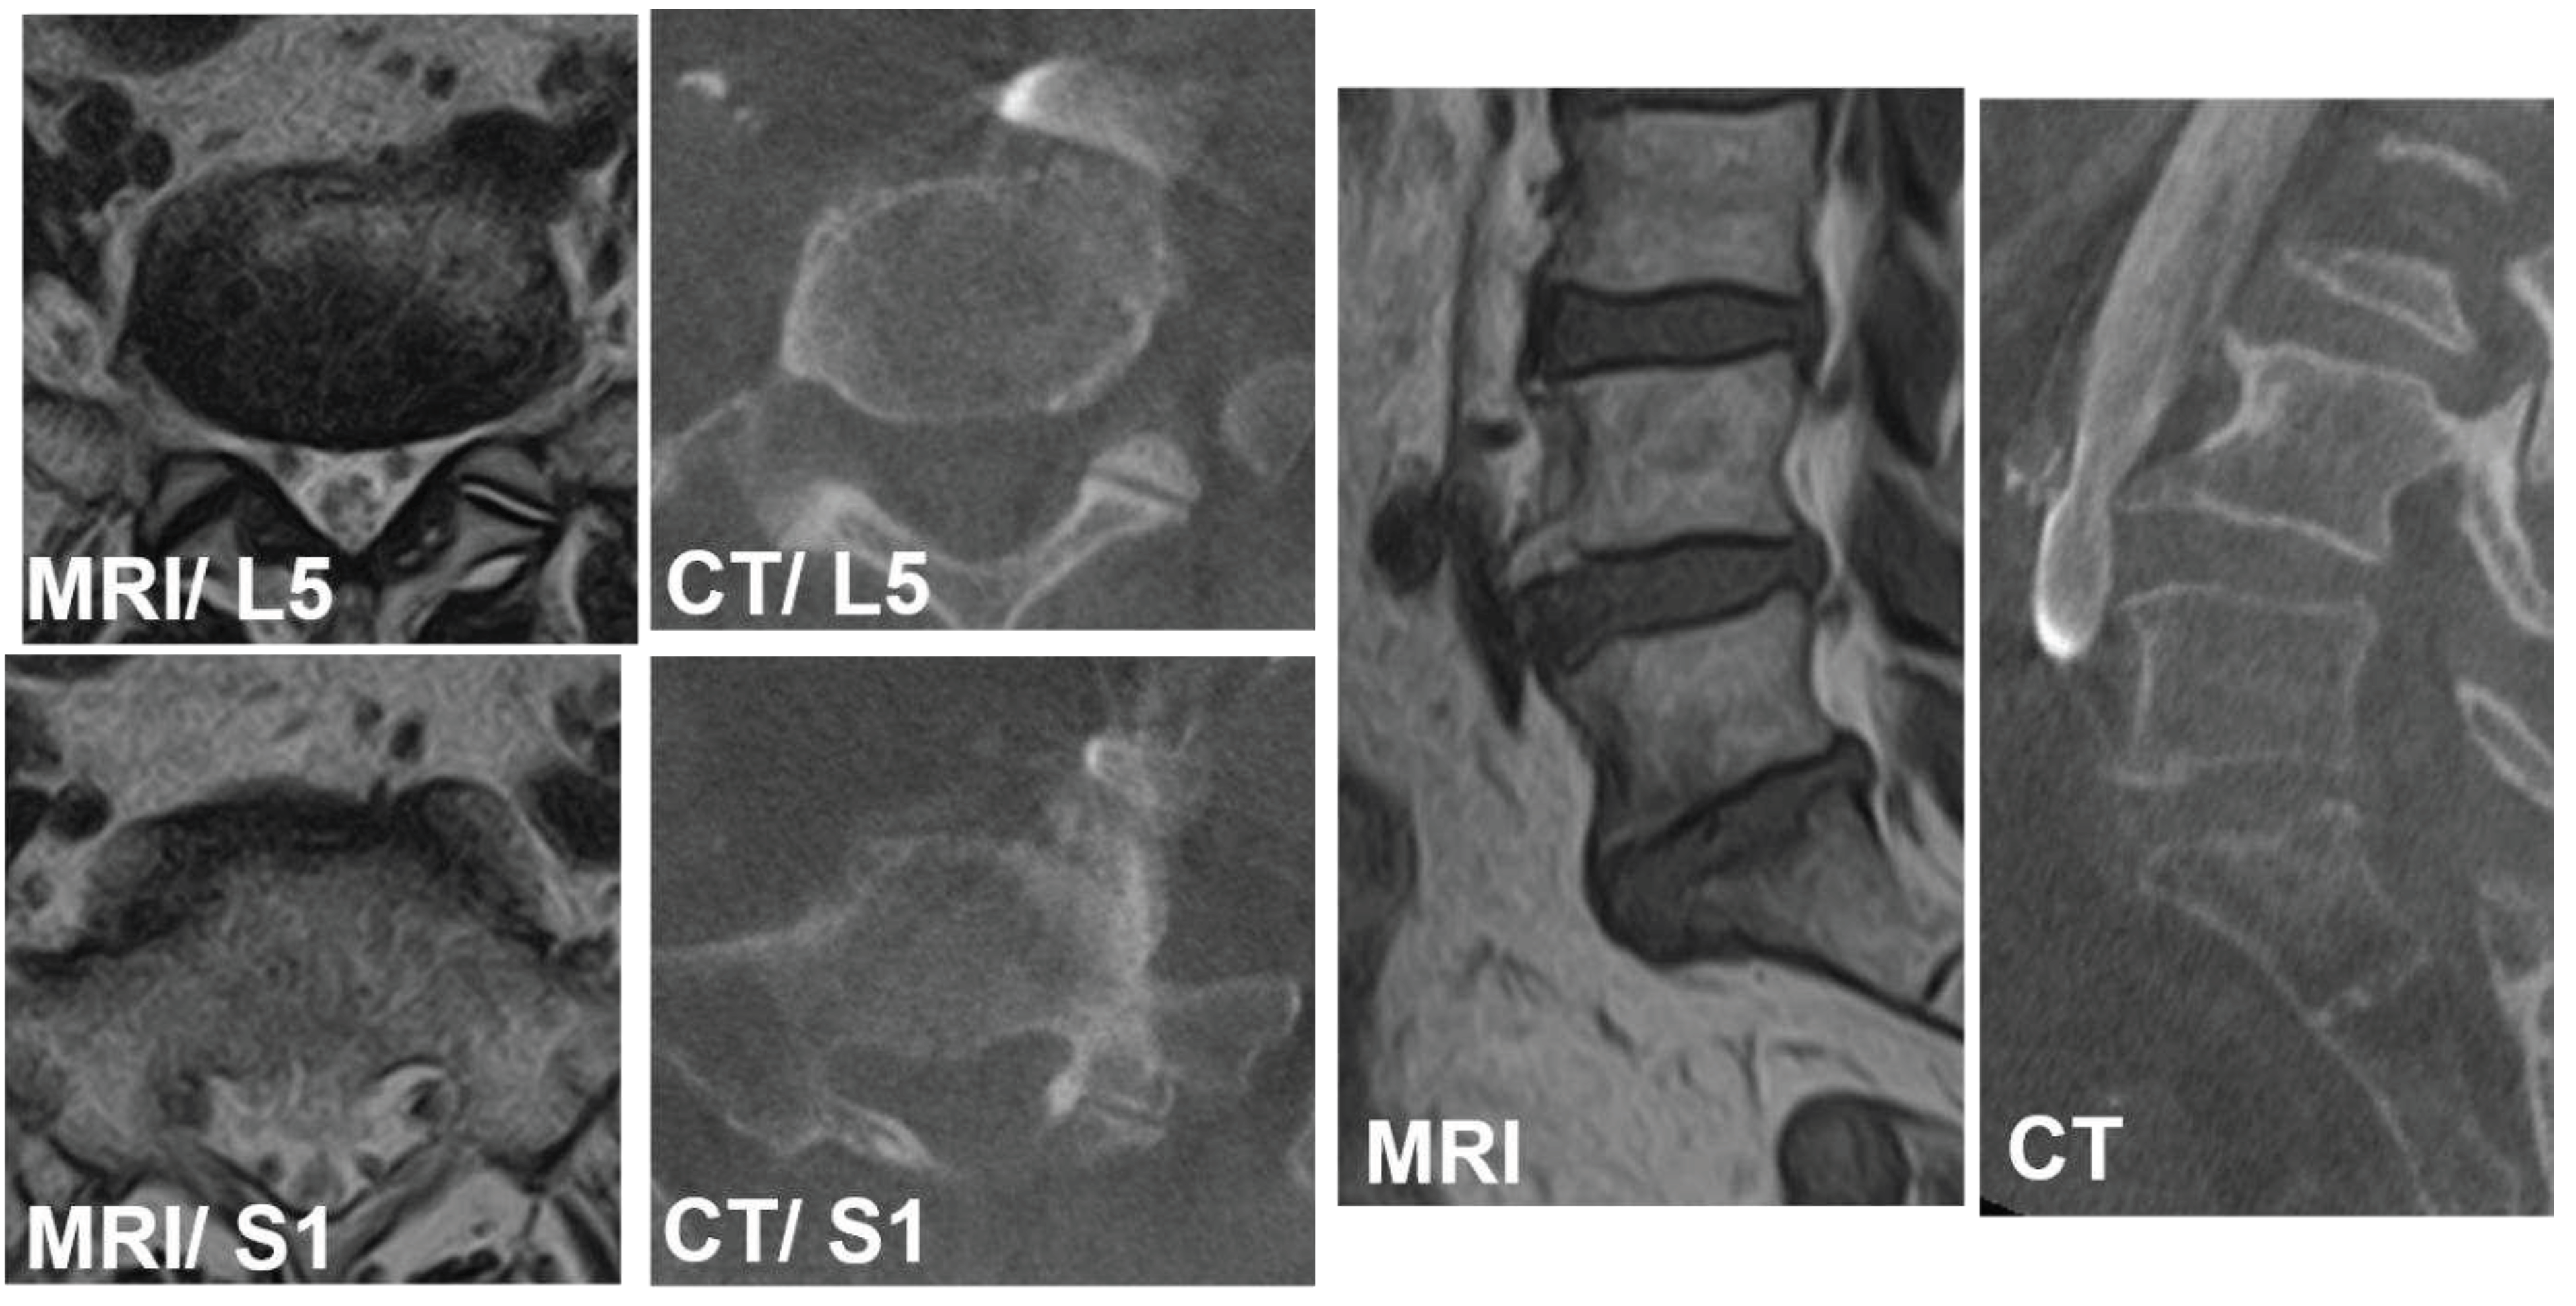

Case 1: 75 years old, female with L4 degenerative spondylolisthesis and L5/S1 degenerative disc disease received L4-S1 OLIF followed by lateral position percutaneous screwing and fixation. The comparison between preoperative supine MRI images and intraoperative vein enhanced CT demonstrated left CIV movement of 6.7mm to right in right decubitus position at L5 lower endplate level, and 3.4mm to right at S1 upper endplate level. The vein bifurcation moved to caudal direction in 8.5mm under right decubitus position (Figure 6).

Case 2: 76 years old female, Pseudarthrosis of L5/S1 transforaminal interbody fusion.

The preoperative CCW was 7.4mm and 9.6mm at L5 and S1 level respectively. The lateral corridor approach was conducted instead of OLIF51 approach. The iliolumbar vein was ligated and interbody fusion was conducted successfully (Figure 7).

Figure 4. Measurement of common iliac bifurcation either on MRI or CT. The position was measured from L5 caudal endplate to bifurcation and expressed as plus (cephalad) or minus (caudal). CIVsagMR: common iliac vein in sagittal MRI; CIVsagCT: common iliac vein in sagittal CT.

Figure 6. 75 years old, female with L4 degenerative spondylolisthesis and L5/S1 degenerative disc disease received L4-S1 OLIF followed by lateral position percutaneous screwing and fixation. The comparison between preoperative supine MRI images and intraoperative vein enhanced CT demonstrated left CIV movement of 6.7mm to right in right decubitus position at L5 lower endplate level, and 3.4mm to right at S1 upper endplate level. The vein bifurcation moved to caudal direction in 8.5mm under right decubitus position.